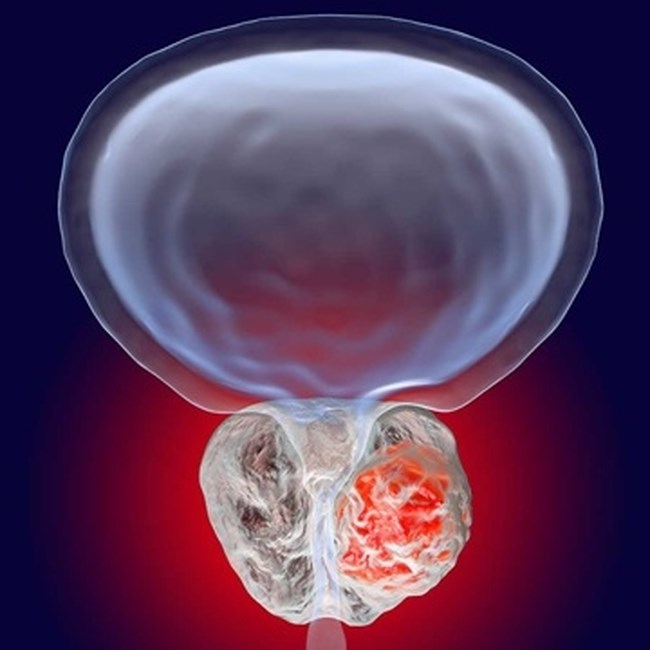

Ο καρκίνος προστάτη αποτελεί τον πιο συχνό αλλά και περισσότερο ιάσιμο καρκίνο στον ανδρικό πληθυσμό, αν αυτός διαγνωσθεί σε αρχικά στάδια. Ακόμη όμως και σε πιο προχωρημένο στάδιο, η επιβίωση είναι μακρά.

Ακριβώς λοιπόν λόγω και της μεγάλης επίπτωσης αυτού του νεοπλάσματος, έχουν προταθεί, υιοθετηθεί και υλοποιηθεί νεώτερες πρακτικές, διαγνωστικές αλλά και θεραπευτικές, ώστε να παρέχεται στον άνδρα ασθενή η ασφαλέστερη, εγκυρότερη διάγνωση με τις κατάλληλες για τον κάθε ασθενή θεραπείες.

Αν τεθεί η διάγνωση, θα πρέπει να συναποφασιστεί από τον ασθενή και τον ουρολόγο του η κατάλληλη θεραπεία.